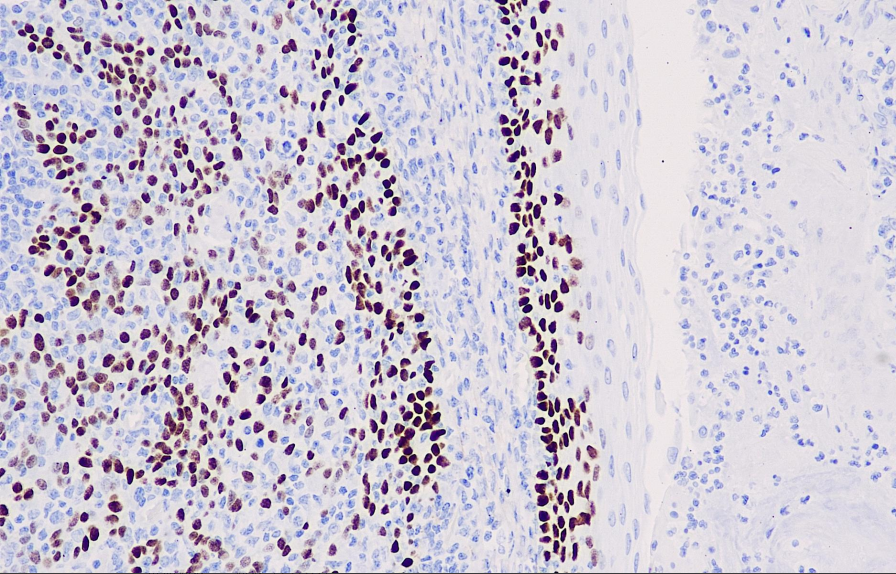

Positive control: tonsils

p40 is one of the subtypes of the p63 protein. p63, as a commonly used reference for squamous cell carcinoma, has extremely high sensitivity. However, due to cross-reactions with a considerable number of lung adenocarcinomas and other tumors (especially lymphoma), its specificity is relatively low. Compared with p63, the sensitivity of p40 in lung squamous cell carcinoma is comparable to that of p63, but it is almost not expressed in lung adenocarcinoma and lymphoma, so its specificity is also very high. Therefore, p40 may replace p63 in the study of lung squamous cell carcinoma.

The p40 antibody reagent can specifically bind to the p40 molecular antigen. The immunohistochemical kit containing the p40 antibody reagent is suitable for prognosis assessment of squamous cell carcinoma (such as lung squamous cell carcinoma and head and neck squamous cell carcinoma).